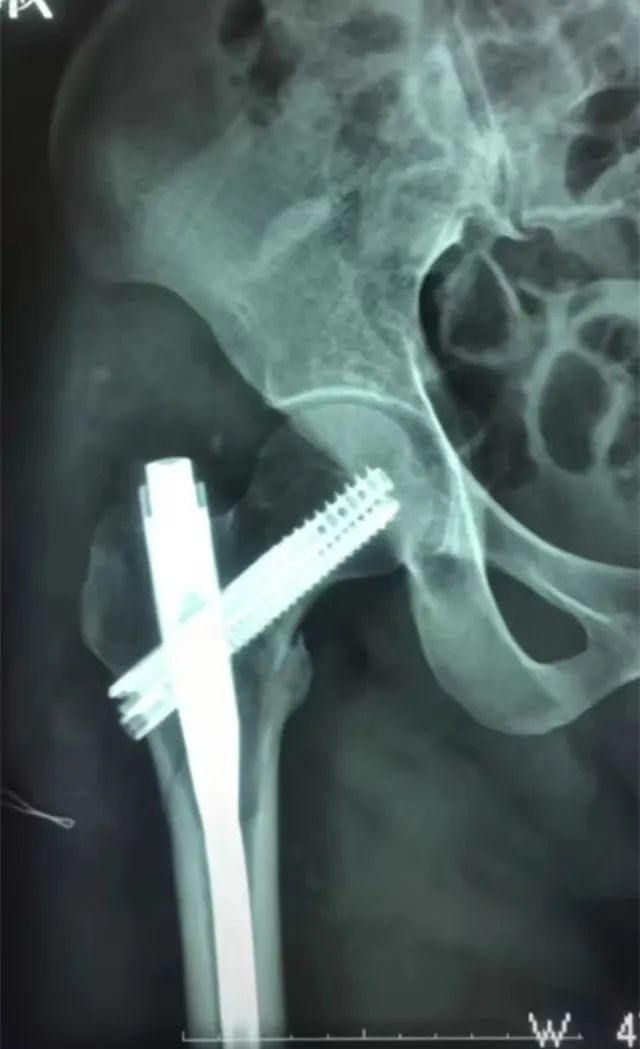

我院首例应用intertan髓内钉固定治疗严重粉碎复杂的股骨粗隆间由骨一

intertan髓内钉治疗中青年粗隆间骨折

intertan在股骨粗隆间骨折的应用及技术要点

intertan 治疗老年性转子间骨折(我院初次尝试intertan技术翻修股骨近

髓内钉intertan与重建钉治疗股骨近端骨折的疗效比较